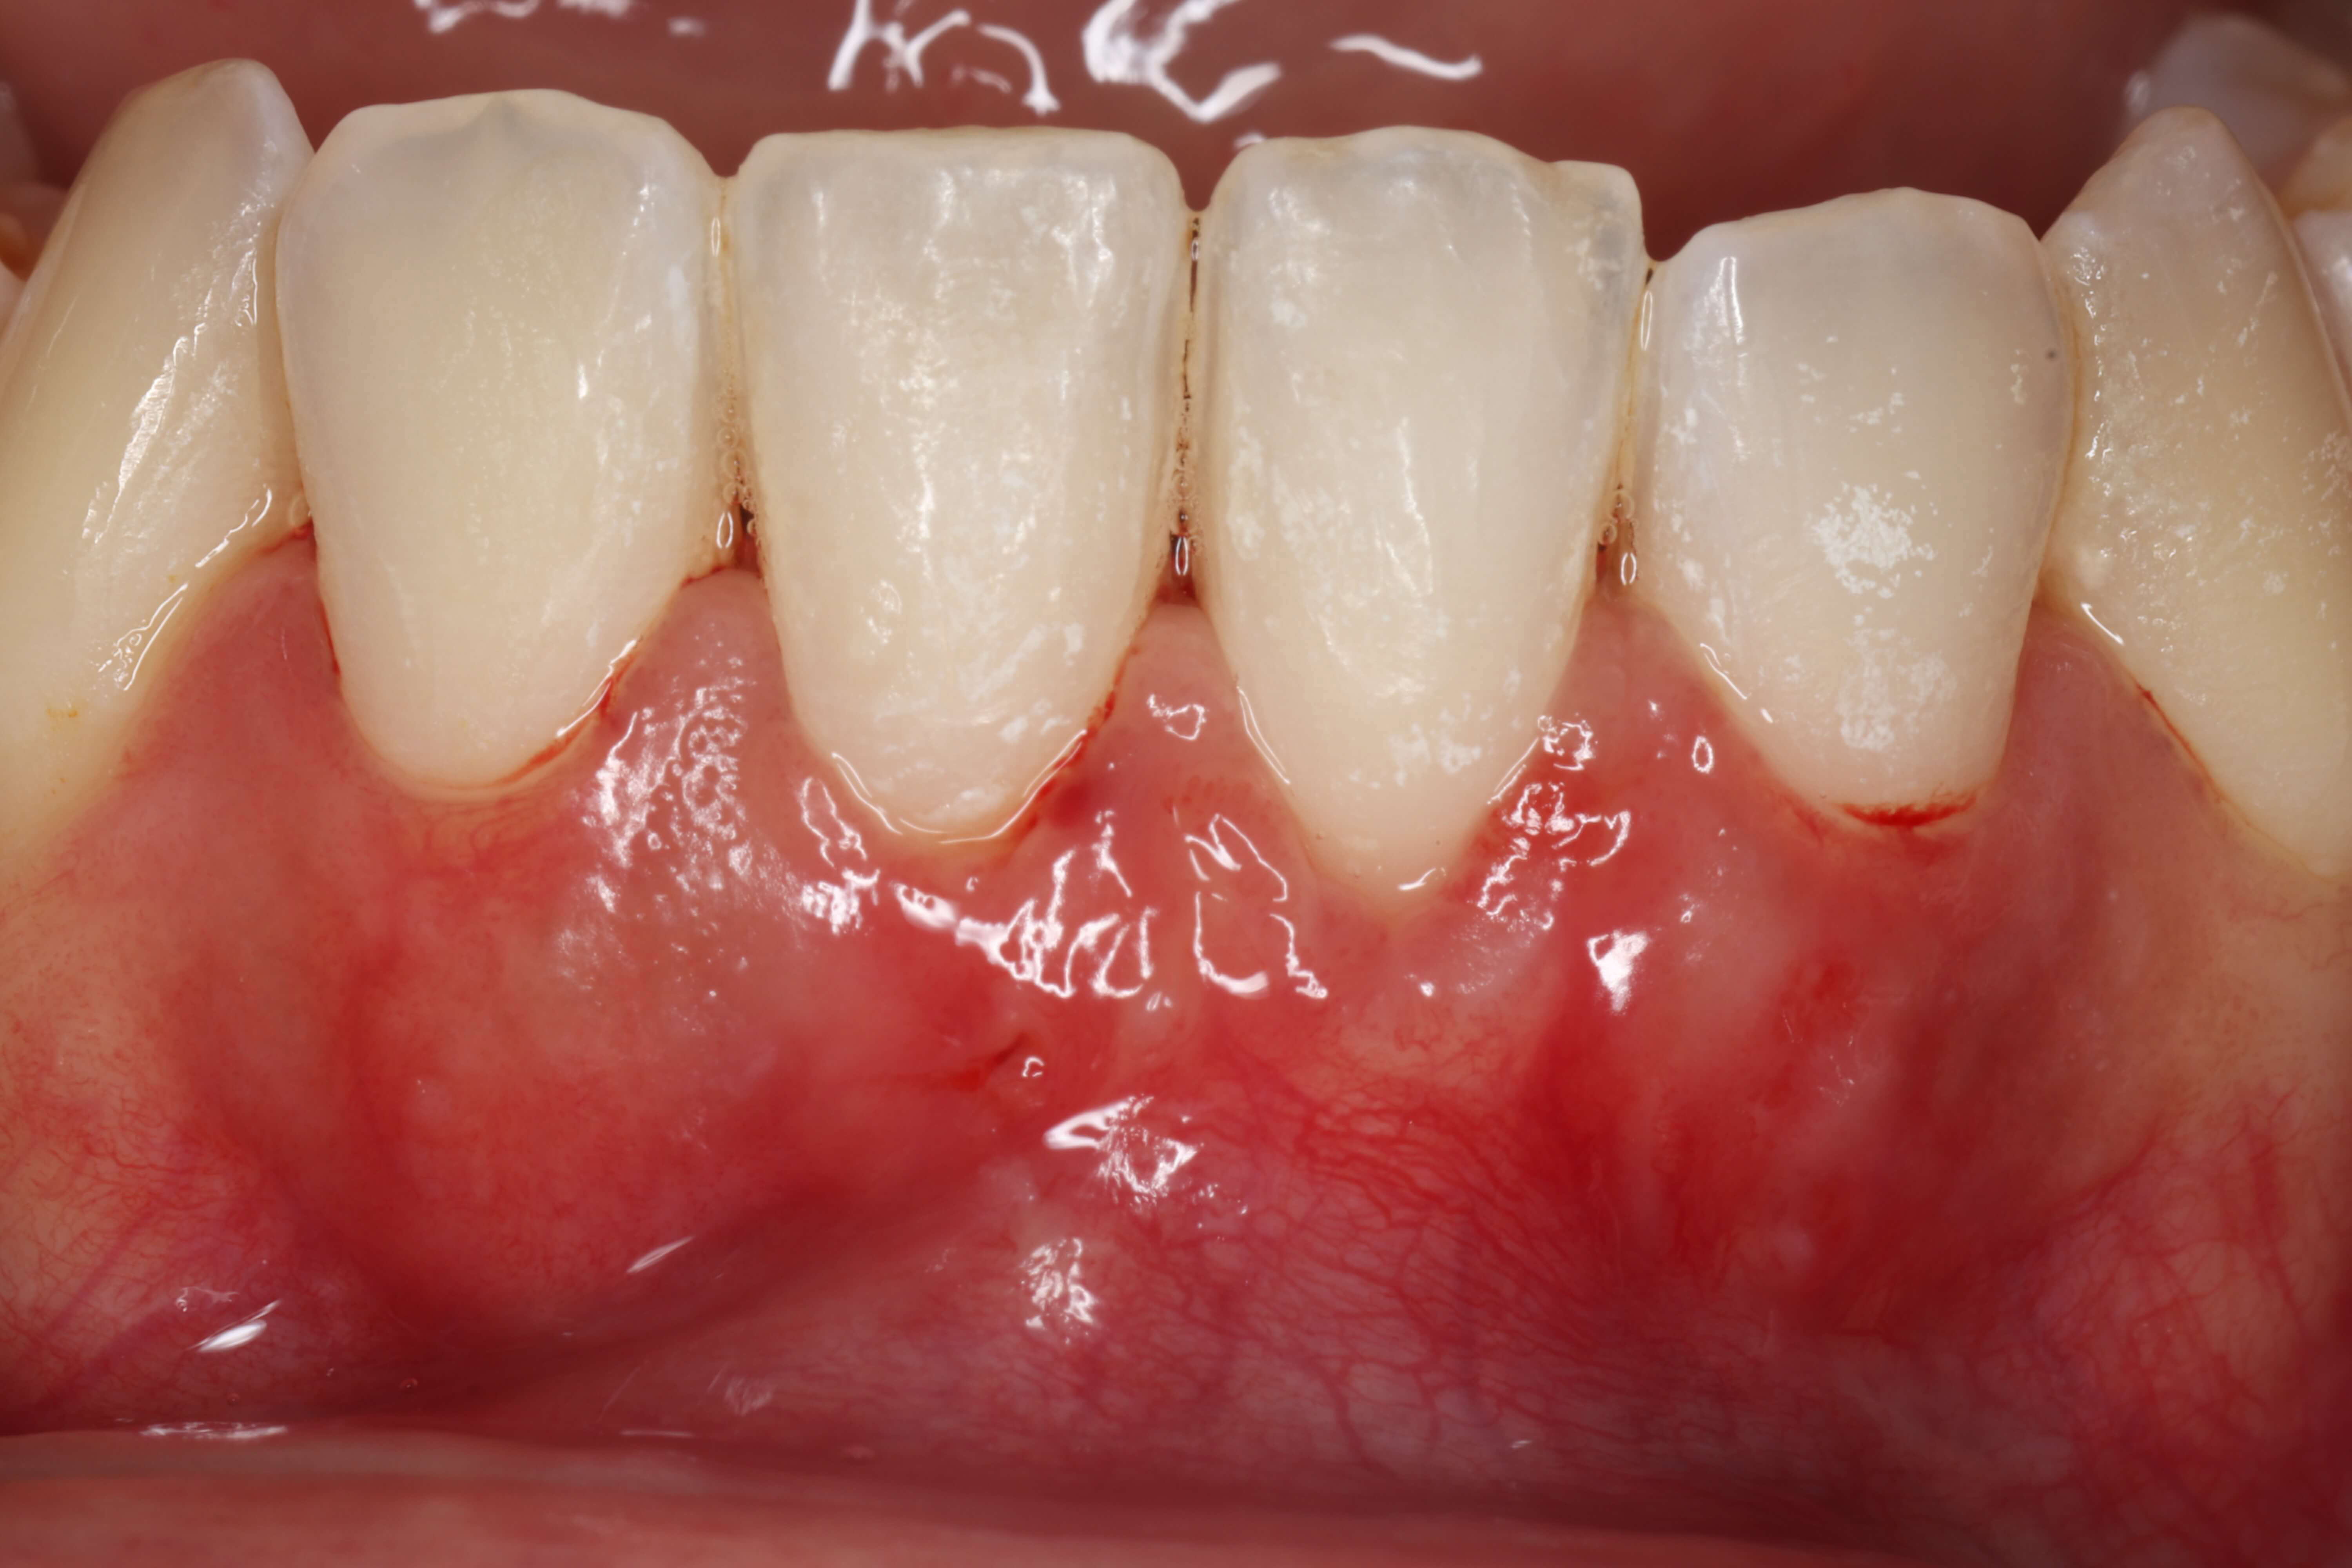

Caso clínico do Dr.º Tiago Rodrigues

A inflamação gengival ocorre devido à acumulação de placa bacteriana e tártaro junto da margem da gengiva. A fase inicial da doença é designada por gengivite e é caracterizada por: sangramento gengival, inchaço da gengiva, mau cheiro e por vezes desconforto ao toque. A gengivite tem uma resolução muito fácil e é completamente reversível. Na ausência de tratamento, a gengivite pode evoluir para periodontite, verificando-se adicionalmente: reabsorção óssea, recessão gengival, mobilidade dentária e eventualmente perda dos dentes. A periodontite quando não tratada é uma das principais causas de perda dentária nos adultos.